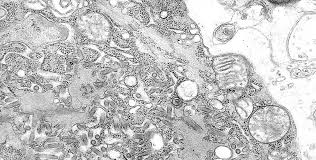

Unter anderem werden die Viren massenhaft im Speichel ausgeschieden. Tollwut wurde früher hauptsächlich durch Bisse von infizierten Füchsen übertragen. Bei einem infizierten Tier vermehren sich die Tollwutviren im zentralen Nervensystem.